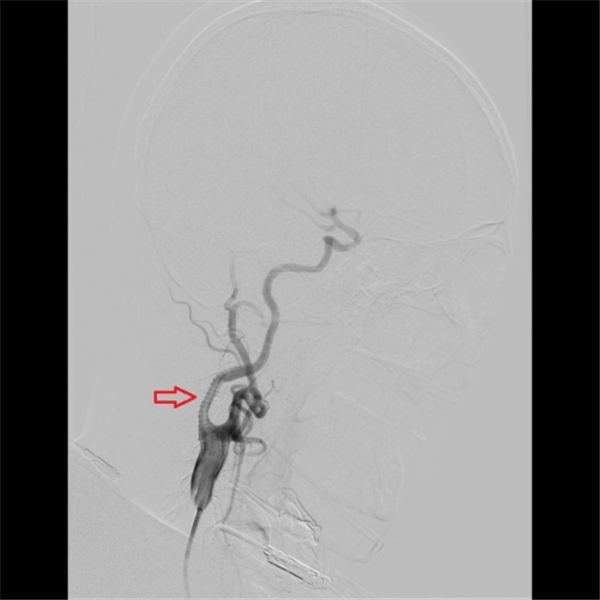

当天,老杜就顺利入住北京燕化医院,第三天就安排了介入手术:在右侧腹股沟局麻之后,穿刺股动脉插管到主动脉,再选择到右侧颈动脉造影,可见右侧颈内动脉重度狭窄、几近闭塞(上图红色箭头)。

确定狭窄部位之后,在微导丝的引导之下,小心的将保护伞(上图红色箭头之间)置于狭窄段远端,以阻拦可能脱落的斑块,避免术中脑梗塞的发生,手术结束之后再将保护伞回收。